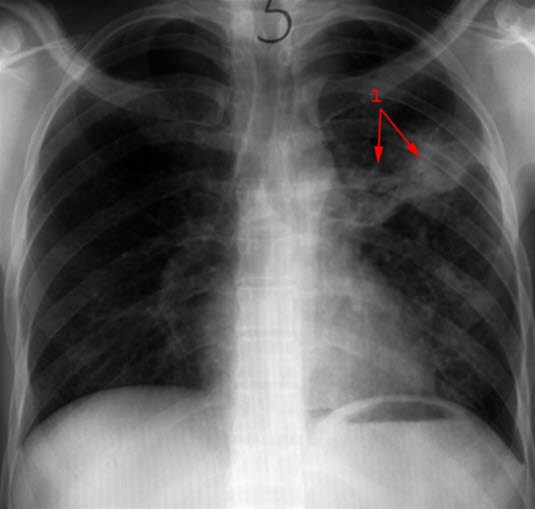

Primær tuberkulose

Utbredte fortetninger spesielt venstre lunge (1)

Før behandling

Primær tuberkulose - bilde 1